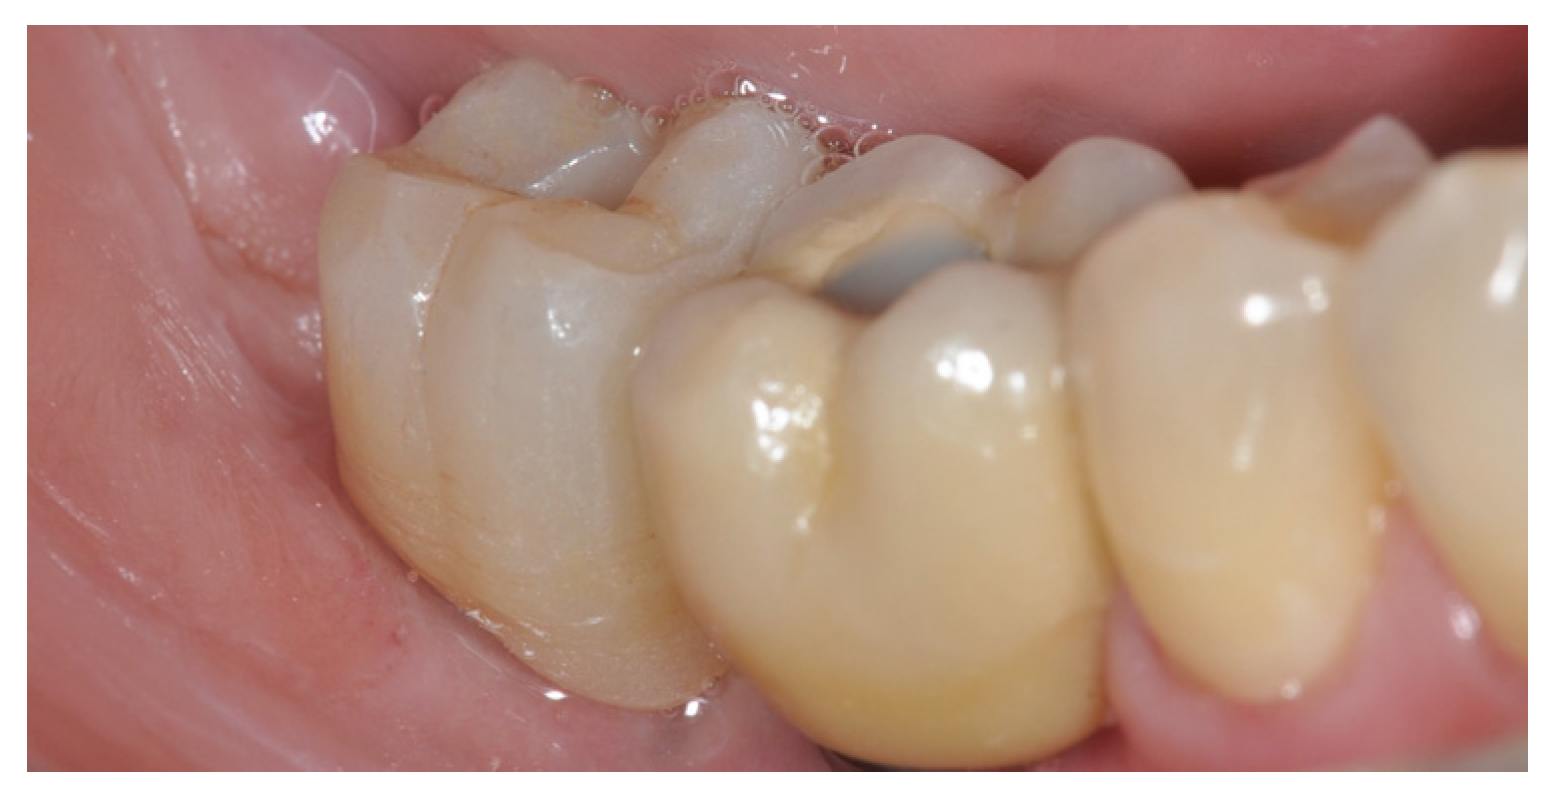

3. Results